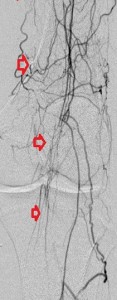

Key to images:

Top panel: Pre-intervention run-off angiogram of the left lower extremity showing, from left to right, irregular left common femoral artery (LCFA) arrowed on the 1st image, absent left superfical femoral artery (LSFA) or any bypass conduit on the 2nd image, sketchy descending collaterals from the left deep femoral (LDFA) that reconstitute a faint shadow of the left popliteal artery, arrowed on the 3rd image. The last 2 images faintly show three-vessel run-off below the left knee. The anterior tibial artery is most opacified, followed by the posterior tibial artery; the peroneal artery peeps through the upper edge of the last image. Note how weakly visible these vessels are due to the poor inflow from above.